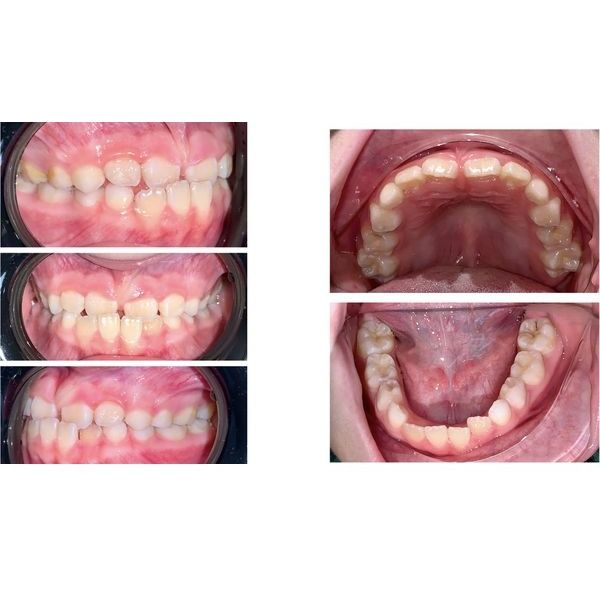

Слизистая оболочка полости рта бледно-розовая, умеренно влажная, без патологических изменений. При смыкании челюстей верхние резцы (зубы 1.1 и 2.1) располагались позади нижних. Правый верхний резец был повёрнут по часовой стрелке, левый — против. Нижний левый резец (зуб 3.2) смещён в сторону языка.

Оба зубных ряда были расположены в форме полуэллипса.

После осмотра пациентке сделали фотопротокол (фотографии лица и зубов), панорамный рентгеновский снимок и сканирование зубных рядов, на основе которого напечатали диагностические 3D-модели, после чего провели их антропометрическое исследование.

Перекрёстный прикус, язычное положение зуба 3.2 и поворот зубов 1.1 и 2.1.